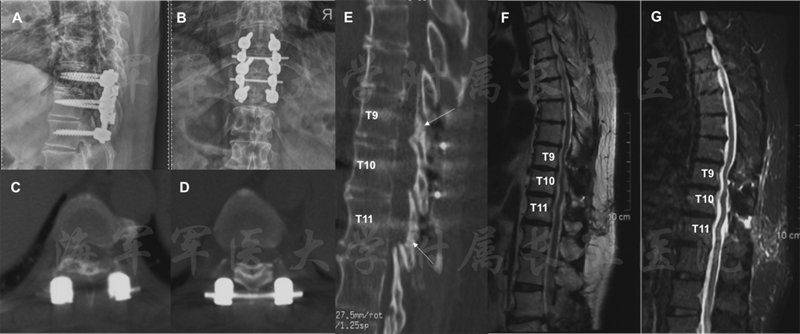

在术后6个月的随访中,病人未出现手术相关的的并发症。病人的肌力由术前的1恢复到最后随访的4.下肢运动和感觉障碍也得到了明显的恢复,病人可以不需要辅助独立行走。病人的泌尿系统功能也得到了明显的改善。JOA评分恢复率在随访的3月和6月分别为50%和75%。术后影显示脊髓获得了充分的减压,脑脊液带也获得了满意的恢复。在最后的随访中,X线提示“吊桥”位置良好,患者植骨也得到了很好的融合。

图7 患者术后6月随访影像学资料